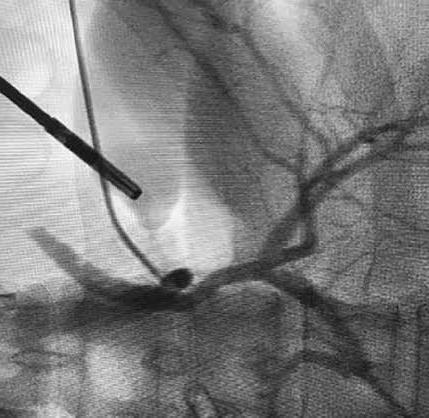

Hintergrund

Die Gallengangverletzung (GGV) stellt eine gefürchtete Komplikation der Cholezystektomie dar; gemäss Literatur tritt sie in ca. 0.3–1.5 % der Operationen auf. Sie ist mit einem erheblichen Morbiditätsrisiko vergesellschaftet, wobei in schweren Fällen eine Hepaticojejunostomie notwendig werden kann, in Einzelfällen gar eine Lebertransplantation. Eine routinemässige intraoperative Cholangiographie (IOC) soll einerseits bei der Klärung der biliären Anatomie helfen und andererseits die Rate an bereits intraoperativ diagnostizierten GGV erhöhen. Eine frühe Erkennung und direkte Behandlung von GGV reduziert die Kosten und erhöht gleichzeitig die Lebensqualität der betroffenen Patienten. Schätzungen ergaben, dass eine routinemässige IOC bei 10’000 Cholezystektomien 2.5 Todesfälle verhindert1. Dennoch wird der Nutzen der routinemässigen IOC kontrovers diskutiert. Das Ziel dieser systematischen Übersichtsarbeit war es, potenzielle Nutzen, Risiken und die Kosteneffektivität der routinemässigen mit der selektiven IOC während Cholezystektomien zu vergleichen.

Als Goldstandard zur Darstellung der Gallengangsanatomie wurde die IOC zuletzt von neueren Methoden wie der Darstellung der Gallenwege durch Indocyanin Grün (ICG) herausgefordert. In einer MetaAnalyse3 mit sieben Studien und 481 Patienten wurden höhere Visualisierungsraten des Ductus cysticus und D. choledochus durch ICG gezeigt. Wobei als weitere Vorteile von ICG eine kürzere Operationszeit und die Einfachheit der Anwendung aufgeführt werden, jedoch können die intrahepatischen Gallengänge nicht dargestellt werden.